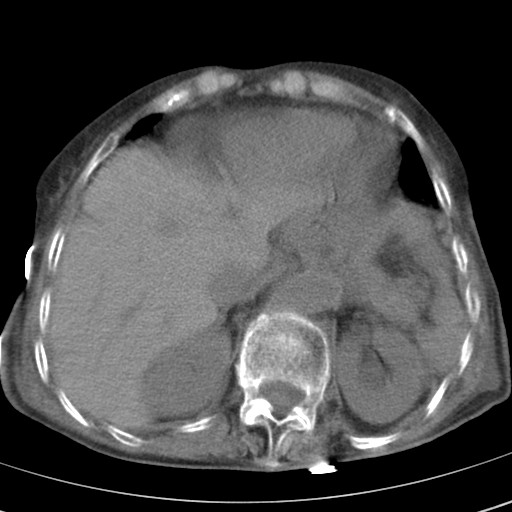

标题: CT21467:女,93岁,摔伤后检查。

女,93岁,摔伤后检查。

右肺炎症,心功能不全伴双侧胸腔积液,右下肺膨胀不全,食管裂孔疝,冠脉钙化,心包少量积液,左侧肋骨骨折,请上传骨窗.

右侧锁骨\\肩胛骨骨折、右侧湿肺,心功能不全伴双侧胸腔积液,右下肺膨胀不全,左膈破裂或食管裂孔疝,冠脉钙化,心包少量积液,请上传骨窗.

右肺炎症,心功能不全伴双侧胸腔积液,右下肺膨胀不全,食管裂孔疝,冠脉钙化,心包少量积液,左侧肋骨骨折,右肩甲骨粉碎性骨折。93岁,高寿哇!

右肺炎症,心功能不全伴双侧胸腔积液,右下肺膨胀不全,食管裂孔疝,冠脉钙化,心包少量积液,左侧肋骨骨折,右肩甲骨粉碎性骨折。